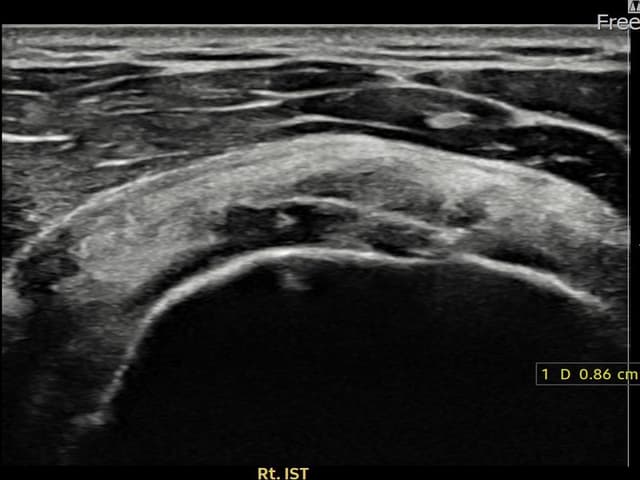

[촬영시기:23.11.28~24.02.06]

[어깨인대 축소봉합술] 우측 어깨 후방 통증과 팔을 바깥으로 돌릴 때 통증이 심해 내원하셨습니다.